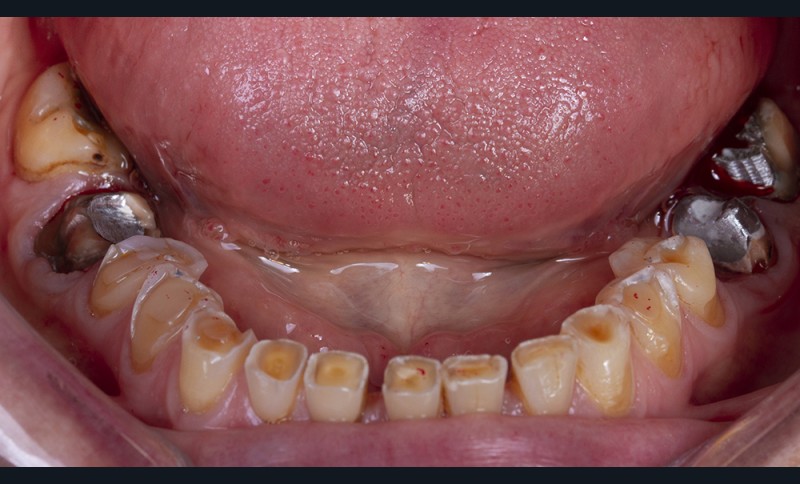

Enfin, une analyse attentive des courbes d’occlusion est menée, notamment dans les cas d’édentements non compensés ou lorsque des restaurations en céramique sont déjà présentes [12] (fig. 1). En effet, la présence de ces dernières peut entraîner une usure différenciée de la dent naturelle antagoniste.

Ainsi, les usures engendrent, dans la majorité des cas, des perturbations au niveau des courbes d’occlusion, lesquelles devront être corrigées lors de la réalisation du wax-up [13].